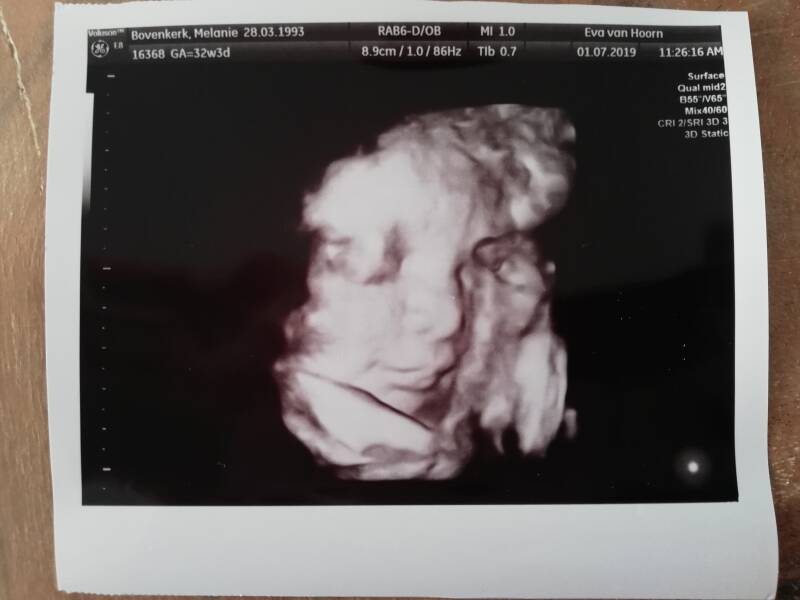

Gisteren hadden we de 3D pretecho van mijn buurvrouw cadeau gekregen, en hebben we ons kleine en erg eigenwijze meisje weer even kunnen zien. Ze hield het nog steeds een beetje mysterieus, maar  voor het eerst hebben we haar gezichtje goed kunnen zien, wel tussen de beentjes en handjes door. Op de vorige echo leek haar 2D profiel heel erg op Aiden maar op deze echo is ze heel erg eigen. Ik vind haar nog niet sprekend op Jim of sprekend op mij lijken maar ze heeft wel Jims ogen! Aiden had echt mijn ogen. Ze ligt wel de afgelopen 3 a 4 echo's in stuitligging, nog niks om me zorgen over te maken hoor ik elke keer. Maar stiekem.... Laten we maar zeggen, dat ze maar gauw mag draaien! Of dat ik haar in ieder geval een keer gedraaid zie zodat ik weet dat ze het kan. Ook lag ze weer lekker in haar favoriete houding met 1 been boven haar hoofd, op haar knietje te sabbelen, en vooral gewoon lekker verstopt achter haar handjes en voetjes. Volgende week weer een gewone verloskunde afspraak zonder echo, en over 2,5 week weer een groeiecho bij de verloskunde praktijk.